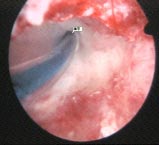

持續性輸卵管妊娠對持續性異位妊娠的處理包括期待療法、藥物療法及手術處理其中以手術方法多見。由於此類患者情況各異,對生育要求不同,因之手術方法亦不一致例如再次輸卵管切開術,部分輸卵管切除及全部輸卵管切除術等。對無症狀的或症狀顯著者則用藥物處理,如用小劑量甲氨蝶呤(MTX)都有輕微副作用,但患者多能忍受,無須再用亞葉酸鈣(甲醯四氫葉酸鈣)可避免第二次手術。少數患者可以經期待療法自愈,因此對PEP的處理應注意個別化。

保守性手術時如何完整地取出妊娠物是預防持續性輸卵管妊娠的關鍵。切口應在輸卵管最突出的部分的中央,可避免漏取妊娠物有人於切口旁註射生理鹽水,將妊娠物整塊衝出也可於術前或術後套用甲氨蝶呤起到預防作用,或手術結束前胚胎著床局部甲氨蝶呤10~25mg。